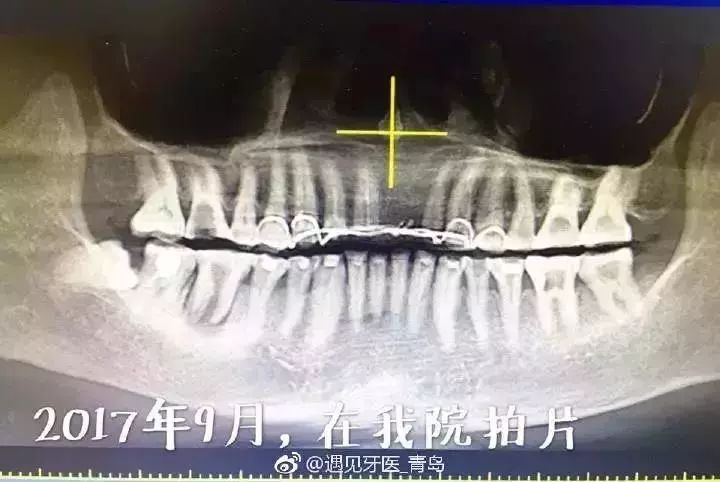

一位阿姨,去年9月份突然进来,问我们这里能不能拍个“很全面的片子”,说牙疼,想都拔了。

拍片后发现阿姨全口29颗牙齿,20多颗都被一个医生已经打开了做神经治疗,一治就是3年,很多牙齿在这三年中每次换药仅仅是处于放棉球敞口“开放”状态!

我跟阿姨明确说:1)拔一颗牙就行,其他牙齿系统治疗后可以用;2)赶紧换医生,不要再去找那个医生了!

今天阿姨再次进门,我一下没认出来,瘦的完全脱相了!一张口我惊了,就在过年前有个医生把牙齿都给她拔了,现在她后悔了,说着说着两眼含泪。

那可是20多颗牙周很健康、很结实的天然牙啊!多少人在这个年龄段,想拥有这么好的牙周条件还得不到呢!